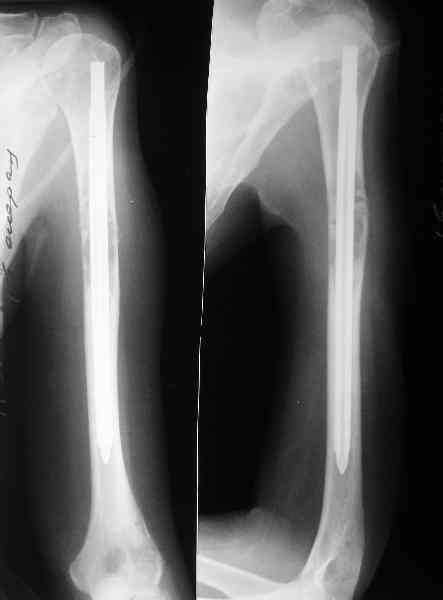

Сегодня сделали, Fixion диаметром 7,4 мм. Обе пперации продолжались по 7 мин. Картинки в приложении. Наркоз был диприваном, на спонтанном дыхании. По крайней мере, пока довольны хотя бы анестезиологи, похоже, не верили, что управимся меньше, чем за час ;-)

Гвоздик 7,4 расширяется до 11 мм. Не маловато ли, судя по снимкам?

7,4 мм, рсширяющийся до 11 мм, в принципе, достаточно для плеча. Хотя мне тоже показалось, что можно было бы и потолще. Вообще есть и следующий диаметр, 8,5 мм, расширяющийся до 13,5 мм, но его в наличии на сегодня не было.